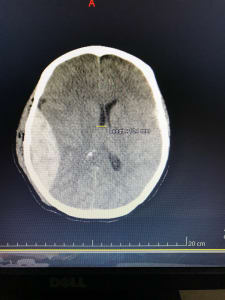

Photo #1: 45 y/o F with a large epidural hemorrrhage. Pt actually came in neurologically intact but after about 3 hours, had a significant change in mental status, she was re-scanned and this is one image from her CT. Ultimately she had a great recovery, and was walking and talking about 5 days later. She did require operative management after being stabilized in the ED, got a burr hole and evacuation of hemorrhage.